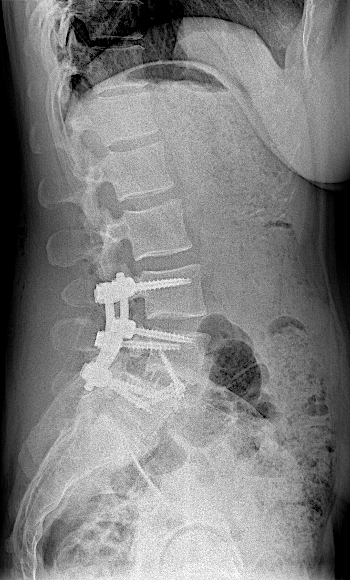

Obsérvese el incremento de la lisis de la pars en las RX dinámicas. La paciente no presentaba clínica radicular significativa por lo que se optó por ALIF L5-L6. El disco L4-L5 presentaba un grado bajo de degeneración.

Tras la intervención, la paciente fue dada de alta sin complicaciones, con corsé y reposo relativo para valorar fijación percutánea en diferido.

Tras retirada de faja, la paciente seguía presentando lumbalgia mecánica. Obsérvese la lisie de la pars.

En la RM lumbar de control se apreciaba edema en L5-L6 que se interpretó como secundario a sobrecarga mecánica a dicho nivel. Se decidió una fijación percutánea (MIS) L5-L6.